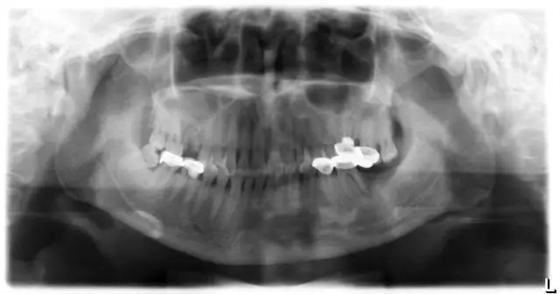

2013.4.11 巨XX 女 38歲

35、36、37烤瓷固定橋修復(fù),35、36為基牙,36烤瓷冠表面大量崩瓷,35探診(—),叩診(—),36探診(+),叩診(+)。

X線片顯示36已行治療,根充不徹底,遠(yuǎn)中根牙周膜增寬,根尖周有暗影。

診斷:35、36、37不良修復(fù)體